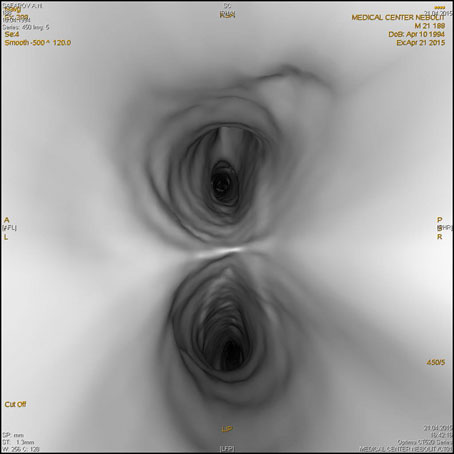

- Программа виртуальной эндоскопии-для просмотра трахеи, бронхов, толстого кишечника